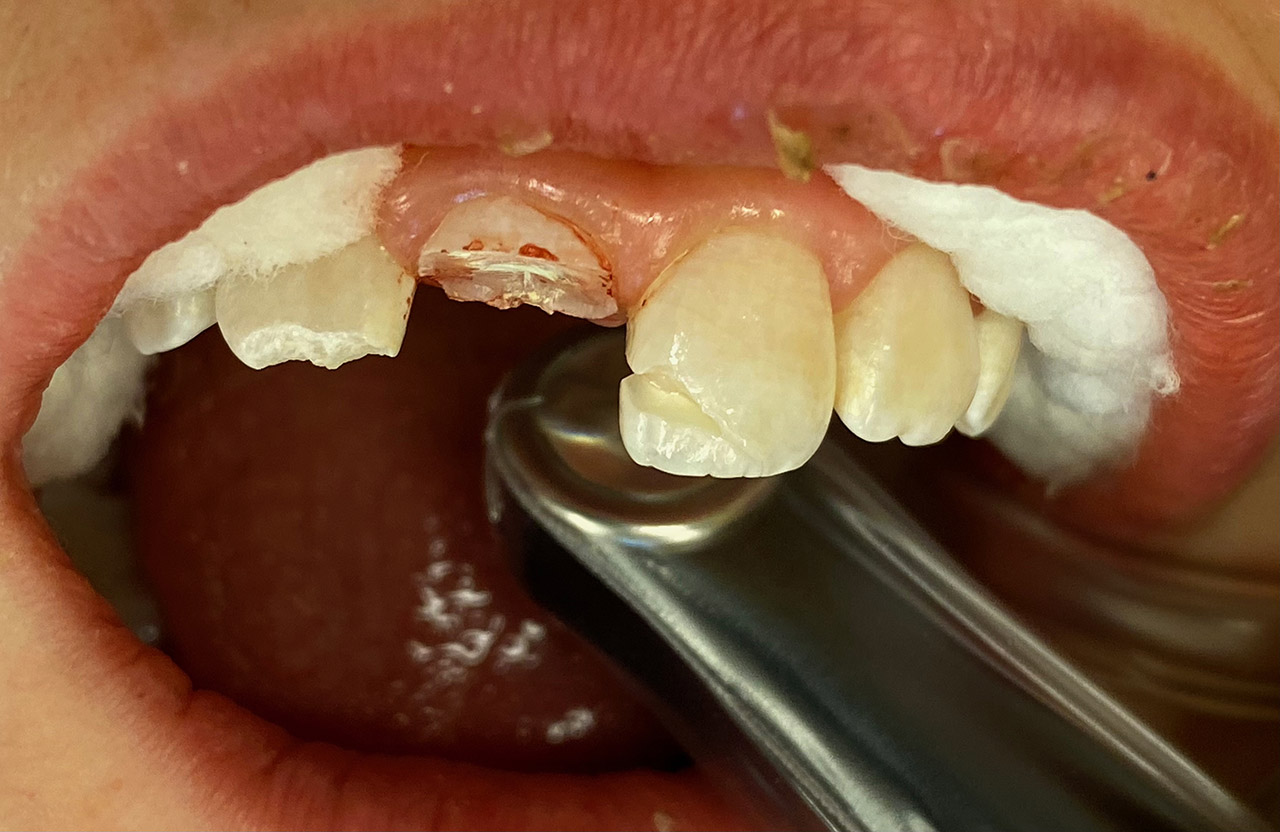

Traumatologie und Endodontie:

Nach Unfall/Sturz mittlerer Schneidezahn auf Gingivaniveau abgebrochen, Pulpa weit eröffnet, beide Nachbarzähne ebenfalls frakturiert.

Erstversorgung: Pulpektomie der Kronenpulpa, MTA, provisorischer Verschluß mit rosa Glasionomerfüllung.

Wiederaufbau der Nachbarzähne mit mitgebrachten (plus 1 Stein) Zahnstücken mit Kunststoff ergänzt und adhäsiv verklebt.

2. Schritt nach Aushärtung von MTA: Entfernung der Kronenpulpa im Bruchstück zur Vermeidung von Verfärbung, Füllung mit Kunststoff.

Adhäsives zementieren des abgebrochenen Zahnstücks.